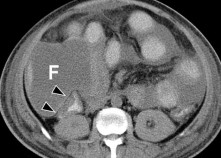

Hình 1.23. Chụp CLVT tiêm cản quang, nhiều vết rách và tụ máu nhu mô gan.

Hình 1.24. Phim chụp lại thấy khối tụ máu dưới bao mới phát triển do chảy máu muộn (mũi tên).

Nguồn: Shanmuganathan K, Mirvis SE [21].

Áp xe gan hoặc quanh gan: Tỷ lệ 0,6% đến 4% [20, 28]. Trên phim chụp CLVT trước và sau tiêm thuốc cản quang, ổ áp xe là khối tỷ trọng dịch, trong

lòng có thể có hơi. Thành khối áp xe bắt thuốc cản quang, đường viền giảm tỷ trọng do phù nề tổ chức xung quanh.

Hình 1.25. Áp xe gan sau CTG trên phim chụp CLVT (mũi tên).